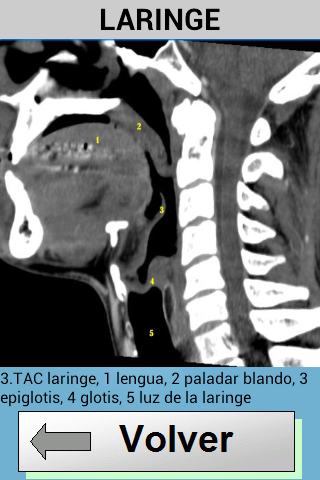

Tato aplikace se naučí snadno identifikovat anatomické struktury, které lze vidět v radiologii.obsahuje obrázky prostých rentgenových snímků, MRI a CT skenů.

Také s každým obrázkem je vysvětlení, které lépe porozumí.

obsahuje obrázky hlavy, páteře a hrudníku.